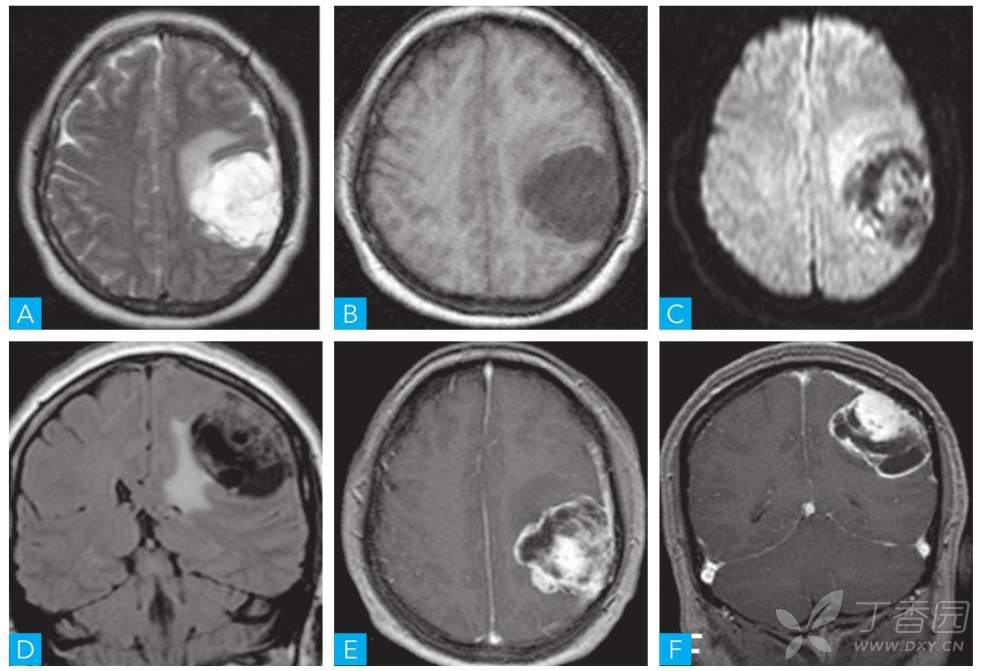

病例【影像诊断与鉴别031】中年女性,突发精神烦躁, 呼唤睁眼, 沟通困难,请分析~~

女性, 44岁。 病人于半天前突发精神烦躁, 呼唤睁眼, 沟通困难,余(-) 。

根据影像,最可能的诊断为何?

胶质母细胞瘤35 人

脑膜瘤12 人

室管膜瘤5 人